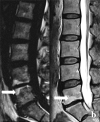

Figure 4.

Type I Modic Change (left) and Type II Modic Change (right). With permission by: Chen, Y., Bao, J., Yan, Q., Wu, C., Yang, H., & Zou, J. (2019). Distribution of Modic changes in patients with low back pain and its related factors. European Journal of Medical Research, 24(1). https://doi.Org/10.1186/s40001-019-0393-6.